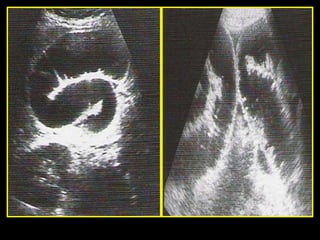

Indirect evidence

 Rarely identification of occlusion of SMA / SMV.

 Dilated bowel loops and bowel wall thickening

 Pneumatosis intestinalis

 Air in portal venous system